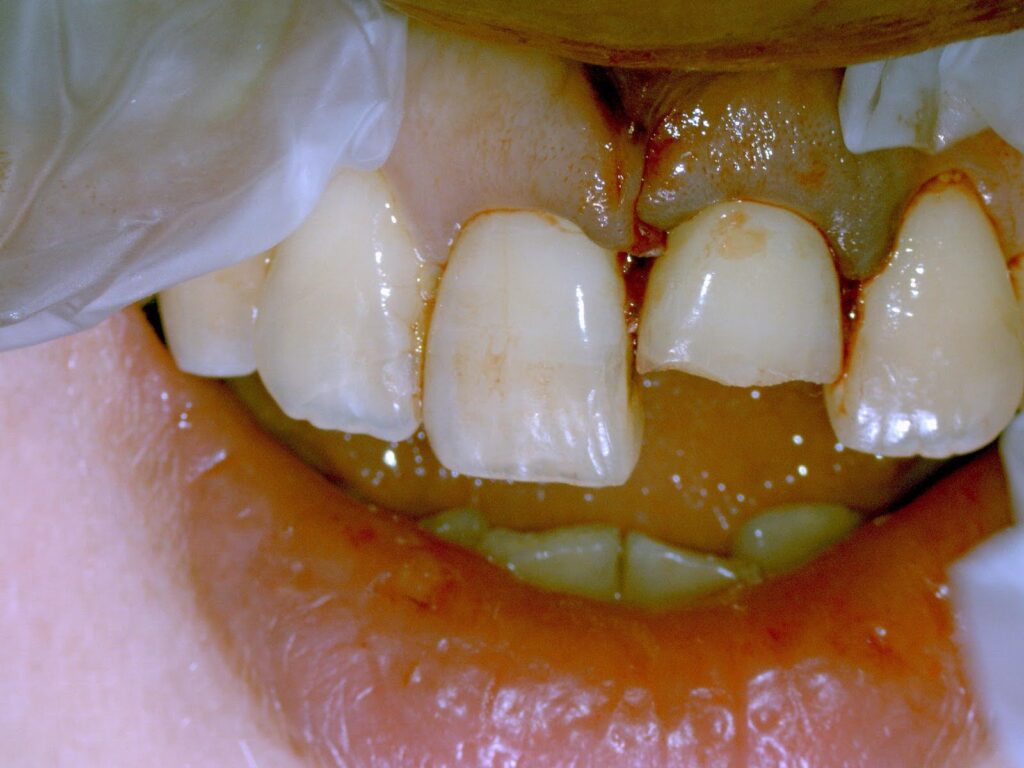

Q3 ぶつけた歯がぐらぐらになった時は?

Dr.:レントゲンと歯髄診断(電気・冷却)から神経の損傷の状態を確認します

12歳未満の場合

症例)

①ベットの上で飛び跳ねていてベッドの背に顔をぶつけた

②友達と遊んでいて友達の肘や頭が自分の前歯に当たった

③鉄棒中に手が滑って鉄棒に前歯をぶつけた

④バスケットやラグビーの練習中に相手の頭に前歯がぶつかった、など)

処置)歯の神経が残る場合があります。すぐにプラスチック(レジン充填)で揺れを止め経過観察をします。

13歳~成人の方の場合

①体育の授業中に同級生とぶつかり前のめりに転倒し床に前歯強打

②幅広のパンツに足が引っかかり前へ転倒

③室内で立ちくらみ、机に前歯をぶつける

④電車内で立ちくらみの為手すりに前歯をぶつける

Dr.:歯の神経(歯髄)は、強打の為断絶してしまい、助かりません。かといって抜歯はしません。壊死してしまった根管内の歯髄を綺麗にする根管治療をします。